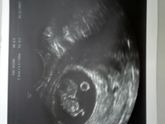

Сегодня нам 8 недель и 4 дня. Выписали из больницы, но уже днём дома рвало...остаётся только терпеть... Выпросила фото на контрольном УЗИ в больнице ?

П.с. пузырик рядом это желточный мешок))

Токсикоз, бррр((( УЗИ сделали, 17 мм мы уже))) говорят, что по УЗИ срок больше, чем по М.

По М 7 недель 5 дней, по УЗИ 8 недель 3 дня.Почему так? Это плохо?